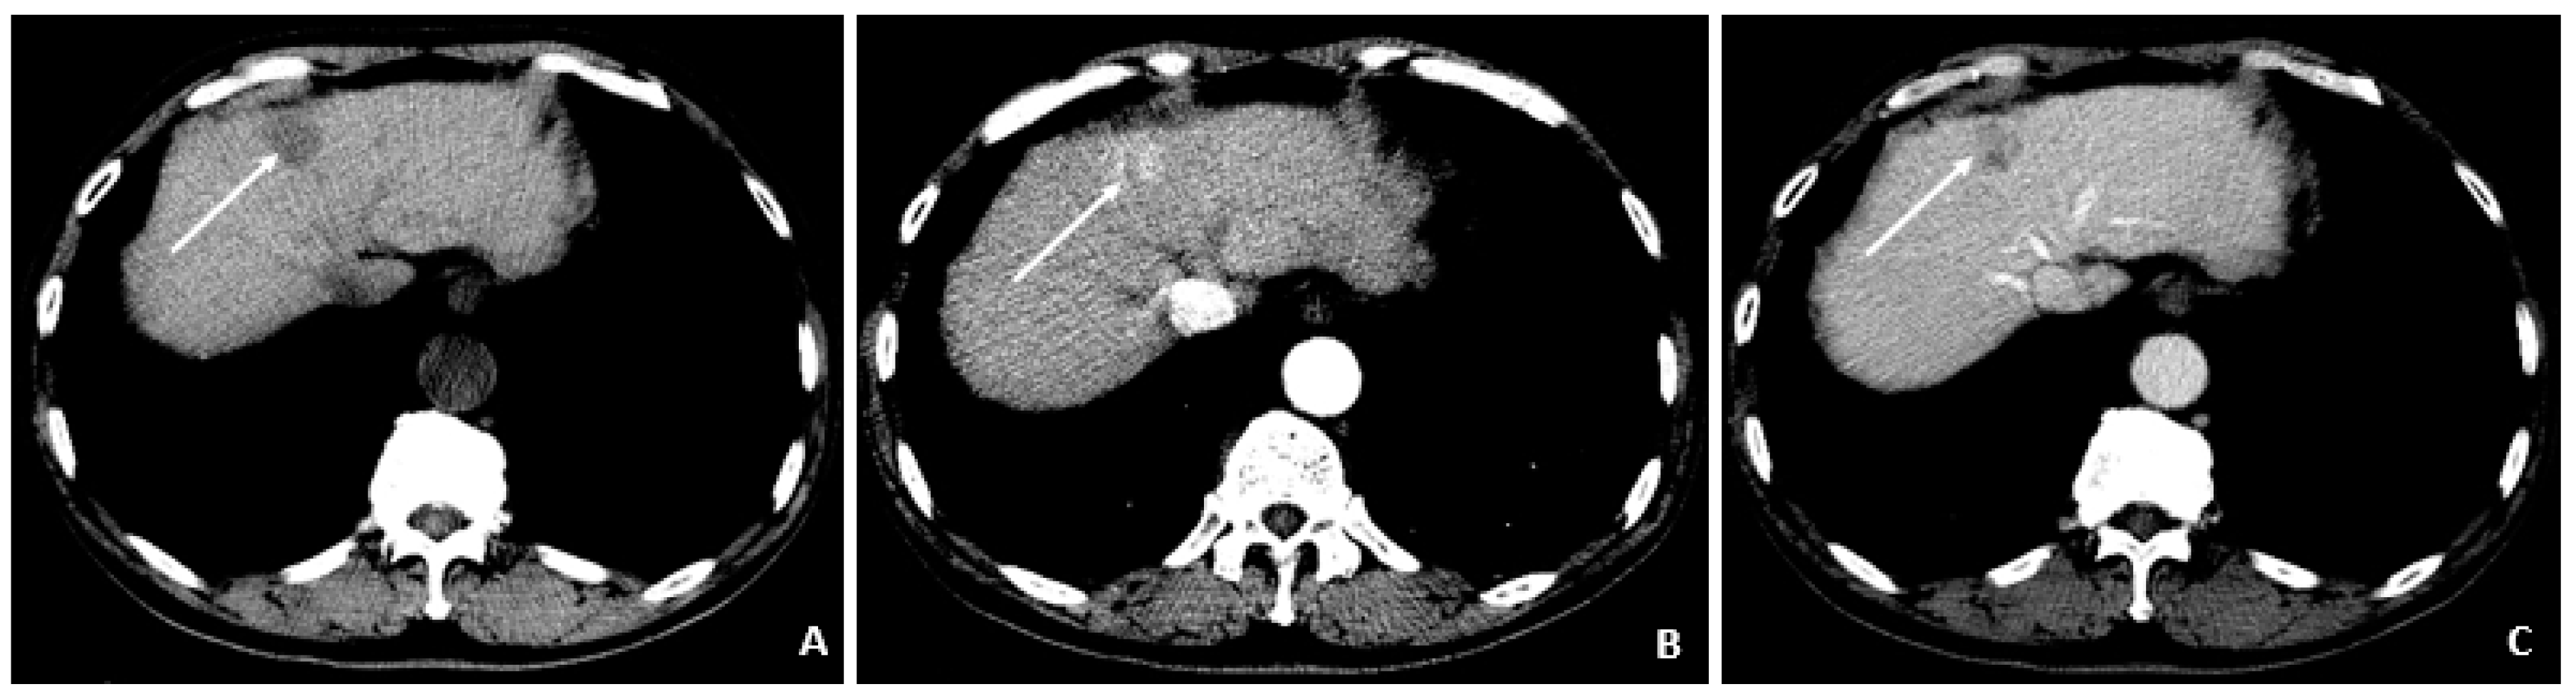

A 58-year-old male was found to have CHB on a routine examination in May 2007. HBV DNA was 4.6 × 105 copies/mL. He was started on telbivudine. The AFP was 3.2 ng/mL in May 2008 with AFP-L3% of 13.8. The MRI in July 2008 showed cirrhosis and no tumor. In August 2008, the AFP remained low at 3.2 ng/mL, but there was a rise in the AFP-L3% to 33.6. The AFP-L3% continued to rise to 69.7 by November 2008, while the absolute AFP value remained at 7.9 ng/mL. In March 2009, the AFP rose to 24.1 ng/mL, and the AFP-L3% at this time was continuing to rise to 87.7. At this time, the abdominal MRI showed a 2.4 × 2.0 cm HCC. He underwent cryoablation followed by radiofrequency tumor ablation and TACE (March and August 2009). These values are outlined in Table 5.

Figure 7.

Recurrent HCC after cryoablation (August 2009 and July 2010). (A) At 3 months following cryoablation, the axial T1-weighted fat-suppressed precontrast image shows a small hypointense lesion (arrow) above and in proximity to the recently ablated HCC. (B) The corresponding arterial-phase postcontrast image shows hyperenhancement (arrow), but additional features (i.e., washout, capsule appearance, etc.) were not observed. (C) Months later, a follow-up MRI showed threshold growth of the hyperenhancing lesion (arrows). (D) The corresponding diffusion-weighted image shows diffusion restriction (arrows) and helps to confirm the diagnosis of HCC (as an ancillary feature); washout was also evident (not shown), confirming the diagnosis of HCC.

Figure 5.

Triphasic CT at the time of HCC diagnosis (March 2009). (A) The precontrast image shows a hypodense lesion (arrow) at the site of the punctate hyperenhancing lesion shown in Figure 4. (B) The corresponding arterial-phase postcontrast image reveals hyperenhancement (arrow). (C) The portal-phase postcontrast image shows washout (arrow), and all features are typical of HCC and confirm the diagnosis in the setting of chronic HBV.